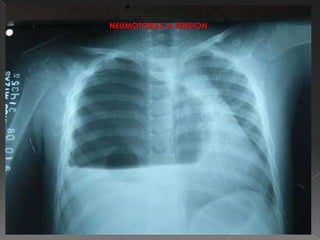

neumotórax a tensión

NEUMOTORAX A TENSION